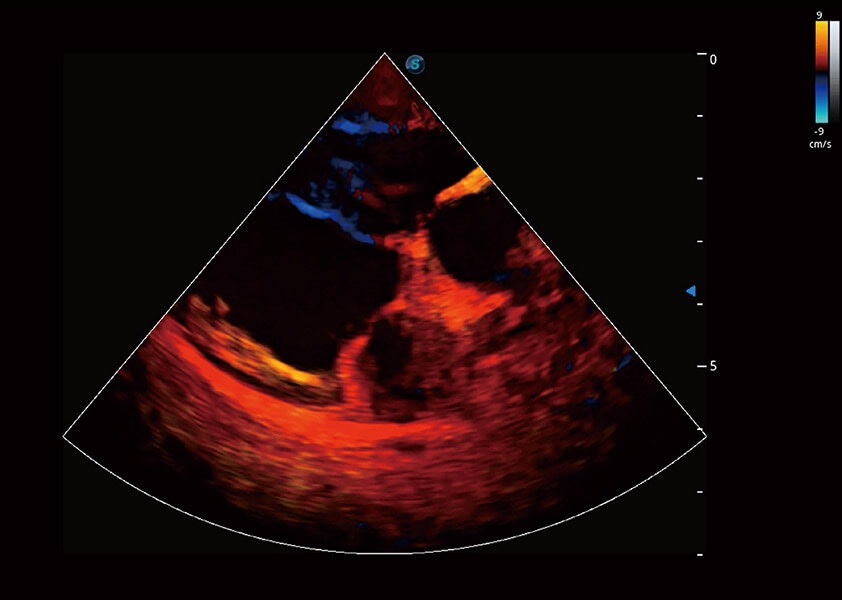

ProPet 60 作為一款高端臺式動物超聲設(shè)備,為動物醫(yī)生的日常診斷提供了一系列貼合動物臨床需求、解決臨床實(shí)際問題的高級成像功能。憑借全系列高清探頭,滿足醫(yī)生對腹部、心臟、生殖、淺表、肌骨等成像的所有需求,切實(shí)幫助您提升檢查效率,提高診斷信心。